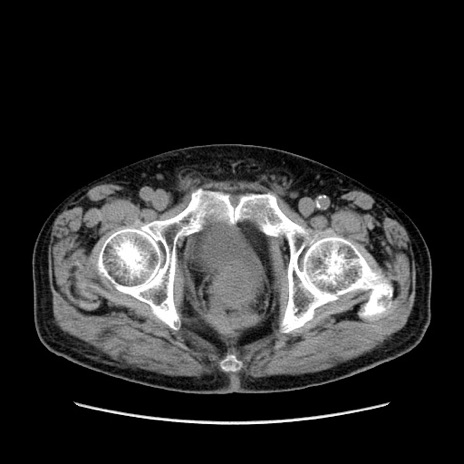

症例24(横断像)

【症例】80歳代男性

【主訴】左側腹部痛、嘔吐

【現病歴】本日早朝より左腹部に痛みあり。昼頃嘔吐認めたため、救急要請。

【既往歴】直腸癌(Mile手術)、胆摘

【身体所見】意識清明、BT 35.9℃、BP 221/93mmHg、SpO2 97%(RA) 、腹部:左ストーマ周囲に限局性の腹部膨隆あり。 膨隆部自発痛・圧痛あり・軟。

【データ】WBC 7700、CRP 0.09